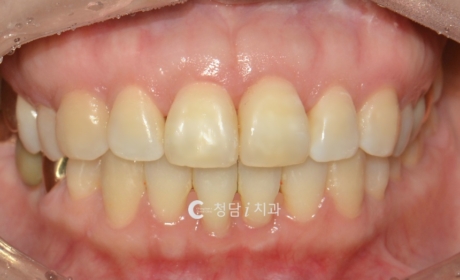

상악 발치로 개선한 과개교합 교정 전후 사례

윗니가 아랫니를 많이 덮는 과개교합은 턱관절에 부담을 주고, 웃을 때 답답한 인상을 줄 수 있습니다.위 환자분은 윗니가 아랫니를 절반 이상 덮는 과개교합으로 내원하셨습니다. 청담i치과에서는 상악(윗니) 부분 발치 후 교정 치료를 진행했습니다. 교정 전: 아랫니가 거의 보이지 않을 정도로 덮여 있던 상태교정 후: 위아래 치아가 자연스럽게 맞물리며, 가지런하고 단정해보입니다.